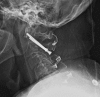

Fractures of the second cervical vertebra (C2, axis) are common in adult spine surgery. Those fractures occurring in younger adult patients are often associated with high-energy mechanism trauma, resulting in a "Hangman's Fracture." Management of these fractures is often successful with nonoperative means, though surgery may be needed in those fractures with greater displacement and injury to the C2-C3 disc. Older patients are more likely to sustain fractures of the odontoid process. The evidence supporting surgical management of these fractures is evolving, as there may be a mortality benefit to surgery. Regardless of treatment, longer-term mortality rates are high in this patient population, which should be discussed with the patient and family at the time of injury. Pediatric patients may suffer fractures of the axis, though differentiation of normal and pathologic findings is necessary and more difficult with the skeletally immature spine.